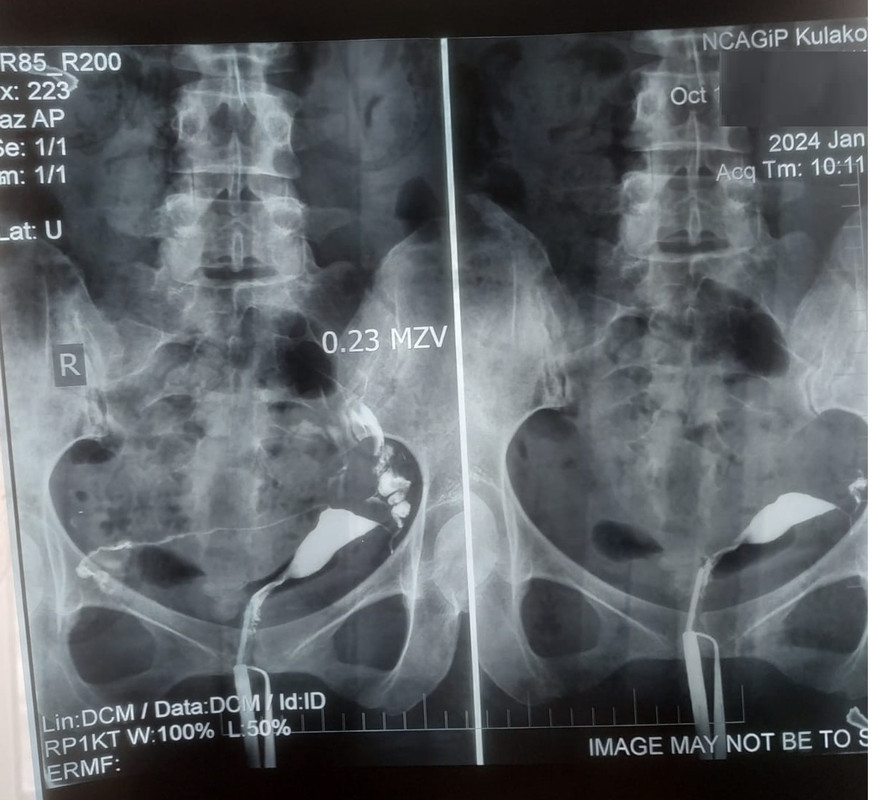

Проходимость маточных труб форум